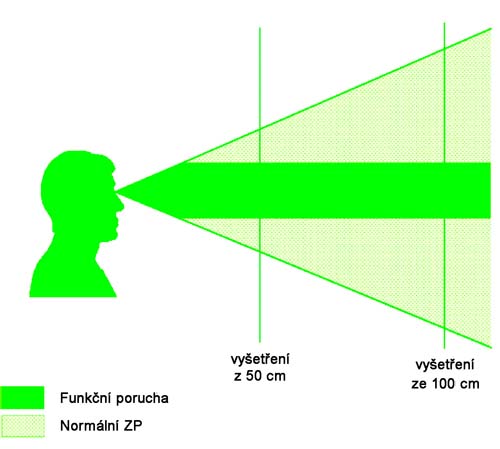

Vlastní pozorování

Náš soubor tvoří 10 žen a 2 muži s koncentrickým zúžením zorného

pole ve věku od 7 do 52 let. Průměrný věk je 25 let, sledovací doba

je několik měsíců až 8 let. U všech pacientů výše uvedené testy

svědčily pro poruchu zorného pole funkčního původu. U většiny

Z našeho souboru vybíráme 3 pacienty, kteří měli typický

charakter nemoci:

1.

Pacientka H.H., nar. 1981 navštívila očního lékaře roku 1992

pro zhoršení vidění. Vizus byl 5/10 vpravo a 5/15 vlevo, zevní i

nitrooční nález byl fyziologický, oboustranně emetropie, jen na

perimetru koncentrické zúžení zorného pole na 10 st. na obou očích.

Testy na možnou funkční poruchu byly pozitivní a vzhledem k